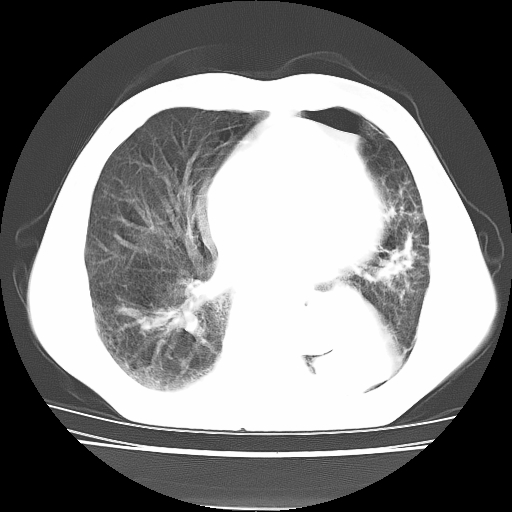

男,71岁,咳嗽,气喘10年,再发并咯血.胸片见气胸

考虑  左肺中心型肺癌伴阻塞性肺炎,肺不张,纵膈淋巴结肿大。慢支炎,肺气肿,左侧气胸肺压缩5%

左侧中央型肺癌伴纵膈淋巴结转移。

左肺中心型肺癌伴阻塞性肺炎,肺不张,纵膈淋巴结肿大

1)考虑左肺中心型肺癌伴阻塞性肺炎、左肺下叶肺不张、左侧肺气肿,纵膈淋巴结转移。2)左侧气胸(肺组织压缩约5%)。

左肺中心型肺癌伴阻塞性肺不张、肺气肿 。

1)考虑左肺中心型肺癌伴阻塞性肺炎、左肺下叶肺不张、左侧肺气肿,纵膈淋巴结转移。2)左侧气胸。